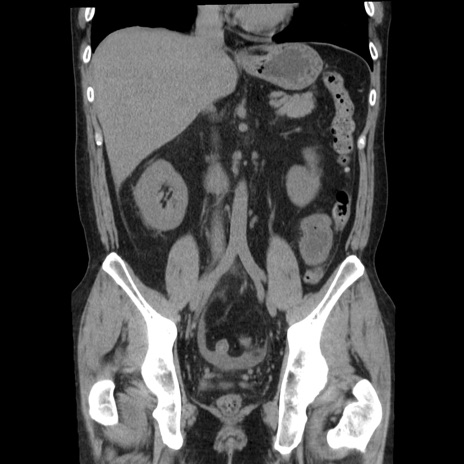

症例29(冠状断像)

【症例】40歳代男性

【現病歴】2日前から胃痛あり。徐々に周期的な激痛に変化した。本日になっても激痛があるため受診。

【身体所見】意識清明、BT 38-39℃台あり、腹部:膨満、やや硬、右下腹部に圧痛あり。

【データ】WBC 8500、CRP 23.26